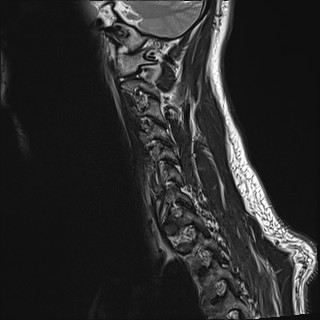

Wirbelsäule HWS

t2_tse_sag